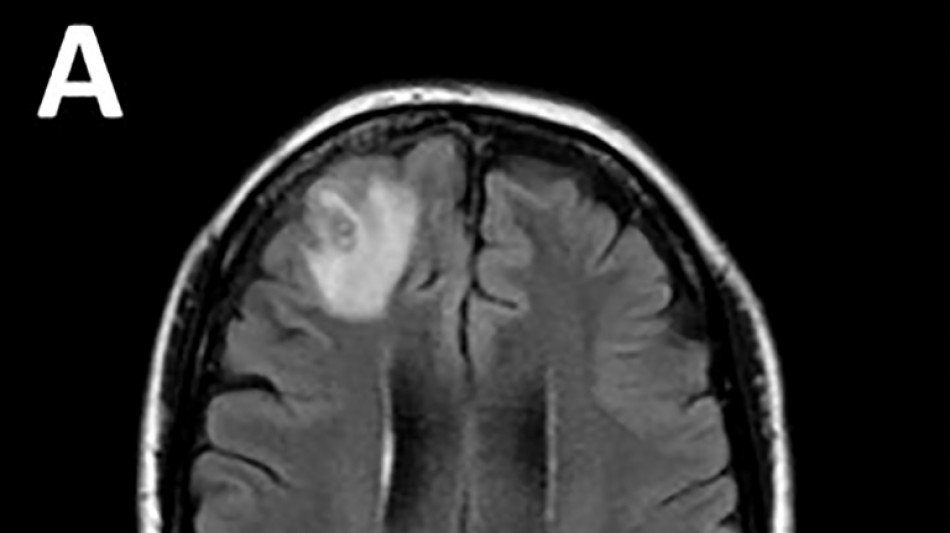

Un ver qui parasite les serpents découvert dans le cerveau d'une Australienne

Un ver rond, qui parasite généralement les serpents, a été découvert pour la première fois sur un être humain, extrait "vivant et se tortillant" du cerveau d'une Australienne lors d'une intervention chirurgicale, ont annoncé mardi des médecins australiens.

Les médecins ont découvert une "lésion atypique", grâce à un examen IRM, dans la partie frontale du cerveau de l'Australienne, âgée de 64 ans, qui souffrait de pertes de mémoire.

Il s'agissait d'un Ophidascaris robertsi, un ver rond de huit centimètres qui, selon les chercheurs, est un parasite des kangourous et des pythons, en Australie. Il parasite des animaux dans d'autres régions du monde, mais il n'avait encore jamais été détecté sur un être humain.

Le parasite, dont la "structure en forme de fil" est apparue sur les scanners cérébraux, a ensuite été identifié grâce à des tests ADN.